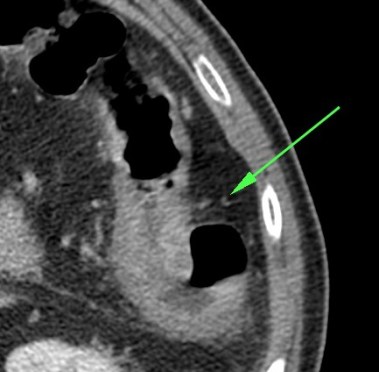

5º) Neumatosis intestinal y portal. Aire extraluminal.

Son signos poco frecuentes pero muy específicos de isquemia intestinal, E cercana al 100%. Se obsevan mejor en el TC SIN contraste.

La neumatosis intestinal consiste en aire localizado en la pared del intestino. Se produce por discontinuidad de la pared con paso de aire hacia las capas más externas y a las venas intramurales.

La presencia de neumatosis portal y mesentérica consiste en pequeñas burbujas de gas dentro de los vasos mesentéricos o que también pueden extenderse hacia las ramas intrahepáticas de la vena porta, encontrándose típicamente en la periferia del hígado.